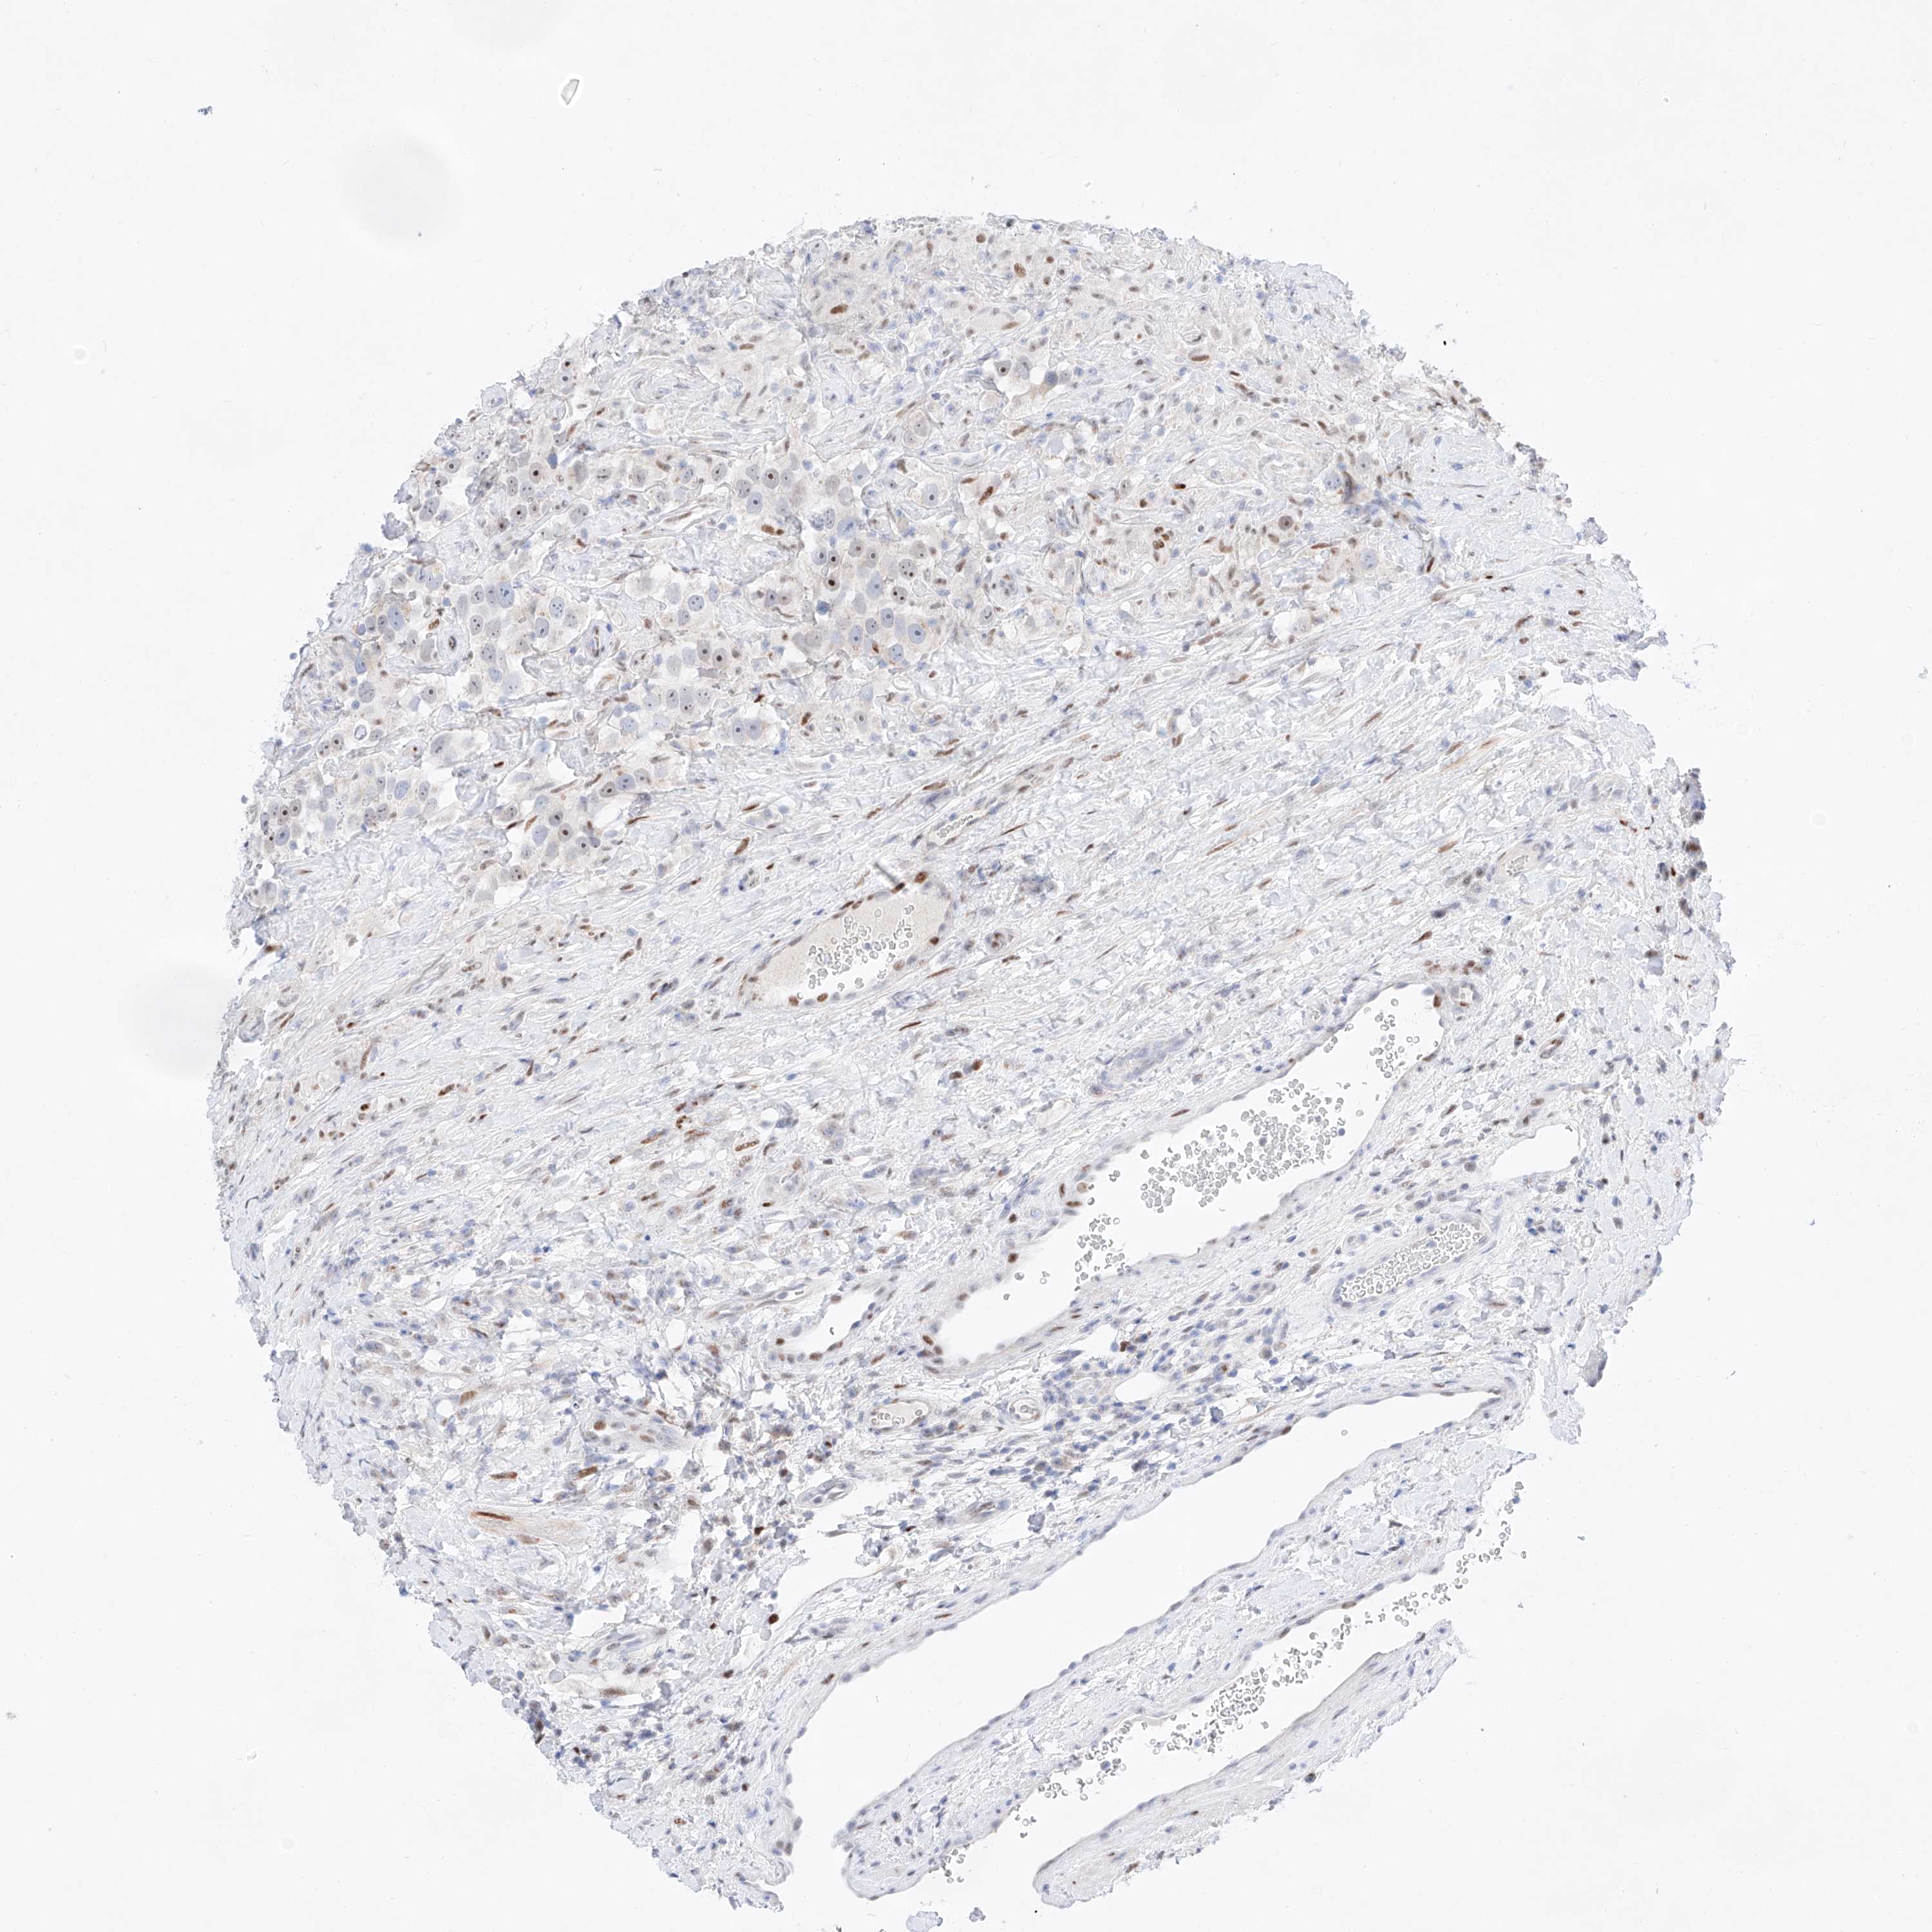

Testis cancer

Human pathology